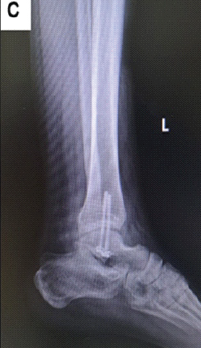

Dual-Screw Fixation for Chronic Syndesmotic Injury: A Case Report

Aya Ewida , Rand Jazmati , Abdulla Abdelwahab , Mohamed Mostafa , Habib Al Ismaily

………………………………p.198-203